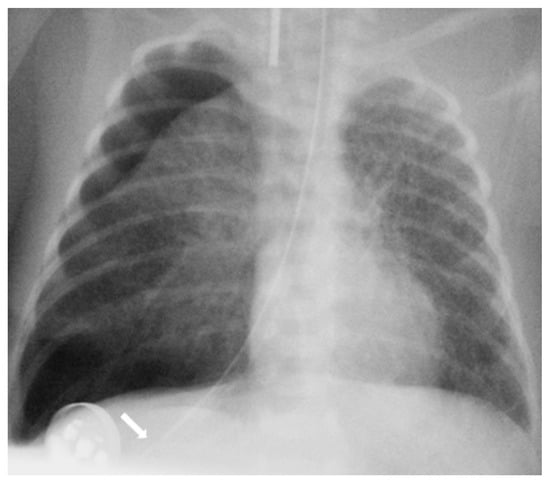

The diagnosis of EP was confirmed via the malposition of the og/ng tube in plain chest X-rays radiographic images. In infants with EP, the chest radiographic image revealed three different malpositions of the og/ng tube. In five infants, the og/ng tube was located in the right pleural cavity (pleural position) (Figure 1), which is usually connected with the pneumothorax or the pneumothorax with pleural effusion, and a radiogram of another two patients indicated mimic esophageal atresia (high position) (Figure 2). In the last three infants, the og/ng tube was located in the abdomen (low position) (Figure 3).

Radiographs of the chest are useful in demonstrating the presence of the og/ng tube in situ and might reveal three different malpositions of the nasogastric tubes, typically in the right pleural cavity associated with right-sided pneumothorax or pneumomediastinum and sometimes pleural effusion. Common symptoms in this situation are connected with the deterioration of the respiratory status. A chest radiographic image may reveal excessive amounts of air in the mediastinum. The high position of the og/ng tube mimicking an esophageal atresia effect may be due to the presence of a mass created by a false passage of air or milk in the mediastinum [9,14]. The position of the top of the og/ng tube may be helpful in differential exclusion. In true esophageal atresia, it is usually above the bifurcation of the tracheae, while in the mimic esophageal atresia, it is located below the bifurcation. In doubtful cases, esophagoscopy can be conclusive [15]. The presence of gas along the og/ng tube may also be helpful in diagnosing EP. The third possible malposition of the og/ng tube involves the intra-abdominal location, which might be associated with the absence of gas in the intestines. It must be noted that a radiographic image cross-table lateral might, in this case, indicate where the tip of the og/ng tube would appear in the posterior/retroperitoneal space. This would be advisable for a more precise diagnosis. Another complication described by Sorens was mediastinal abscess requiring chest drain insertion [16]. Occasionally, patients with intra-abdominal EP might present symptoms of peritonitis or dysphagia and drooling [1]. In our study, like Elgendys’ study, pneumothorax and septicemia were frequent complications of esophageal perforation [17]. We diagnosed peritonitis in one patient and necrotizing enterocolitis in one patient. In one patient, cardiorespiratory decompression was connected to pleural milky effusion. Chylothorax should be considered and excluded upon differential diagnosis when milk is present in the pleural cavity and milky fluid can be aspirated from the right pleural cavity. Kairamkonda linked chylothorax with esophageal perforation, which may follow when the value of the laboratory fluid analyzed shows a triglyceride level of >1.1 mmol/l with absolute cell count > 1000 cells/mcl and lymphocyte fraction > 80% [18,19,20].

Figure 2. Supine AP view of the chest and upper abdomen. The nasogastric tube tip is in a high position below the carina (arrowhead) and can mimic esophageal atresia. Gas outside the esophagus resulted from its rupture (arrow). The umbilical line is present.